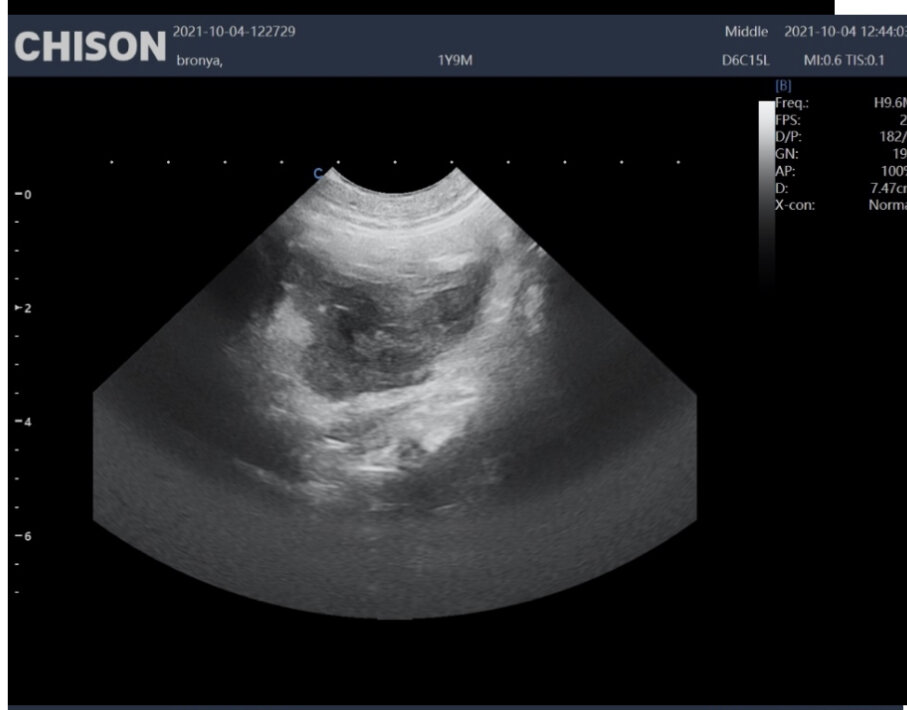

Собака 1 г. 9 мес. Восточноевропейская овчарка. В сторонеей клинике провели плановую овариогистерэктомию. Через сутки послеоперации появились обильные кровянистые выделений из петли и послеоперационного шва.

Была проведена стабилизация состояния, гемотрансфузия. По УЗИ в области анатомического расположения правого и левого яичника визуализируются структуры неправильной формы с не ровным не четки контуром гипоэхогеннойнеоднородной эхоструктуры, имеющие компоненты пониженной эхогенности  округлой формы. Размер структур 2.48 см:1, 38 см и 3, 4 см:2.1 см. Так же визуализируется Предположительновизуализируемые структуры являются гематомами и спаечным процессом с близлежащими тканями

Структура в области правого яичника